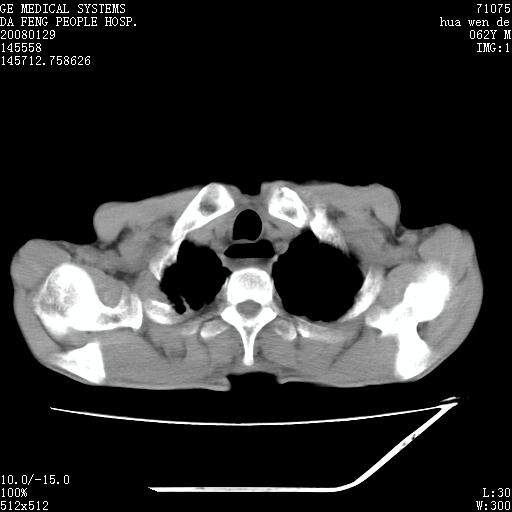

男性,67岁。作肺部检查时发现

考虑:胸腔胃并支气管瘘(并发肺炎,肺脓肿形成)。

理由:1、右上肺内病灶,空洞形成,有液平。

2、肺内多处炎症。

1.整个食管扩张,未见明显占位性病变,贲门区亦未见明显占位病变,考虑:贲门失驰缓症;

食管全程扩张,壁均匀不厚,喷门失弛缓症

右上肺空洞可见液平,临近肺野磨玻璃密度,考虑1.结核2.脓肿

贲门失驰缓症.肺部感染伴脓肿形成。支持!是否吸入性要结合临床诊断,我们影像是看不出来的。但胸腔胃能排除(1.没有手术史支持,2.双侧胸廓对称,胸壁、肋骨及胸膜规整,3,食管壁明显扩张内壁光滑,胸腔胃黏膜皱襞多较厚)。